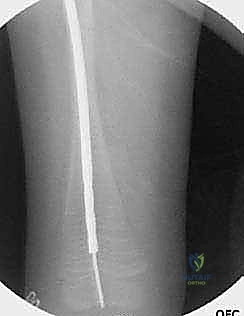

الدليل التفصيلي لخطوات العملية الجراحية: بضع العظم عبر الجلد والمسامير التلسكوبية

تُعد هذه العملية من أدق العمليات في جراحة عظام الأطفال، وتتطلب مهارة استثنائية كما هو الحال مع البروفيسور محمد هطيف. يتكون المسمار التلسكوبي (Fassier-Duval) من جزأين يتداخلان ببعضهما البعض (مثل التلسكوب). يتم تثبيت أحد الأطراف في أعلى العظم والطرف الآخر في أسفله. عندما ينمو العظم، ينزلق الجزء الداخلي من المسمار للخارج، مما يسمح للعظم بالنمو الطبيعي دون أن ينثني أو ينكسر.

الخطوة الرابعة: إدخال المسمار التلسكوبي

بعد تقويم العظم وجعله مستقيماً كحبات المسبحة على خيط، يتم إدخال السلك الدليلي (Guide Wire). ثم يتم إدخال الجزء الخارجي (الأنثوي) من المسمار التلسكوبي وتثبيته في الجزء العلوي من العظم (Epiphysis).

بعد ذلك، يتم إدخال الجزء الداخلي (الذكري) من المسمار عبر الجزء السفلي من العظم وتثبيته في المشاشة السفلية. هذا التصميم العبقري يضمن حماية العظم بالكامل من الداخل.